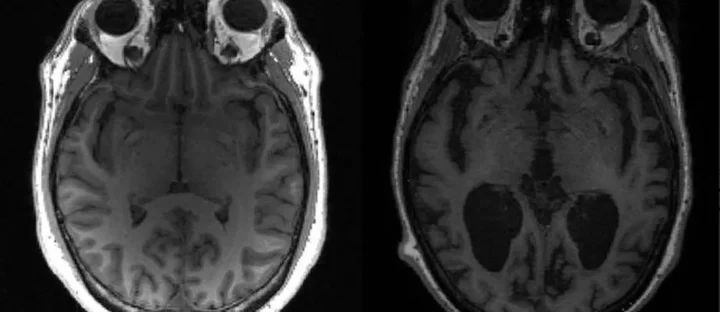

A principal descoberta veio de um grupo internacional de pesquisadores que conseguiu reverter sinais clássicos da doença em modelos animais, incluindo déficits cognitivos e alterações cerebrais associadas ao acúmulo de proteínas tóxicas. O estudo demonstrou que a restauração do equilíbrio energético das células do cérebro, por meio da normalização de uma molécula essencial ao metabolismo neuronal, foi capaz de recuperar funções comprometidas em camundongos com Alzheimer em estágio avançado.

Embora os resultados ainda estejam restritos a testes pré-clínicos, especialistas avaliam o achado como um marco conceitual. Até então, os tratamentos disponíveis tinham como foco principal apenas retardar a progressão da doença. A nova abordagem sugere que, em determinadas condições, pode ser possível reverter danos neurológicos, algo inédito dentro da literatura científica.